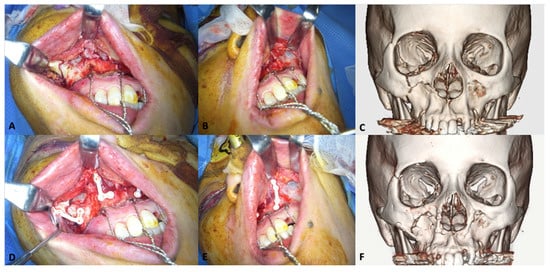

3.1.2. Midfacial Fractures

- Landes, C.; Ballon, A.; Ghanaati, S.; Tran, A.; Sader, R. Treatment of malar and midfacial fractures with osteoconductive forged unsintered hydroxyapatite and poly-L-lactide composite internal fixation devices. J. Oral Maxillofac. Surg. 2014, 72, 1328–1338. [Google Scholar] [CrossRef] [PubMed]

- Sukegawa, S.; Kanno, T.; Katase, N.; Shibata, A.; Takahashi, Y.; Furuki, Y. Clinical Evaluation of an Unsintered Hydroxyapatite/Poly-L-Lactide Osteoconductive Composite Device for the Internal Fixation of Maxillofacial Fractures. J. Craniofac. Surg. 2016, 27, 1391–1397. [Google Scholar] [CrossRef] [PubMed]